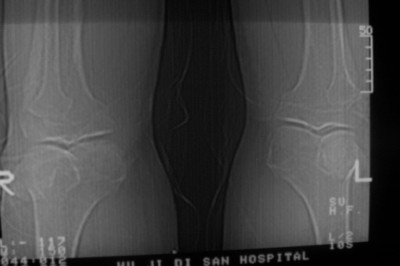

标题: CT8024:会诊!!!男 60 岁 双漆关节疼痛半年,进行性加重 [打印本页]

患者男 60 岁 双漆关节疼痛半年,进行性加重.

左侧股骨下端骨梗死

右股骨内髁关节面下多个不规则小囊变,边缘有明显硬化边,.......考虑: 1.关节面下骨囊变.  2.类风湿关节炎?   3.血友病?

膝关节退行性变,最好是结合x线平片

右侧髁间隆突变尖,软骨下假囊肿形成,结合病人年龄较大,首先考虑退行性骨关节病。关节周围软组织未见明显异常,病人单单一双膝关节出现症状,不太支持类风湿性关节炎,可结合化验室检查。